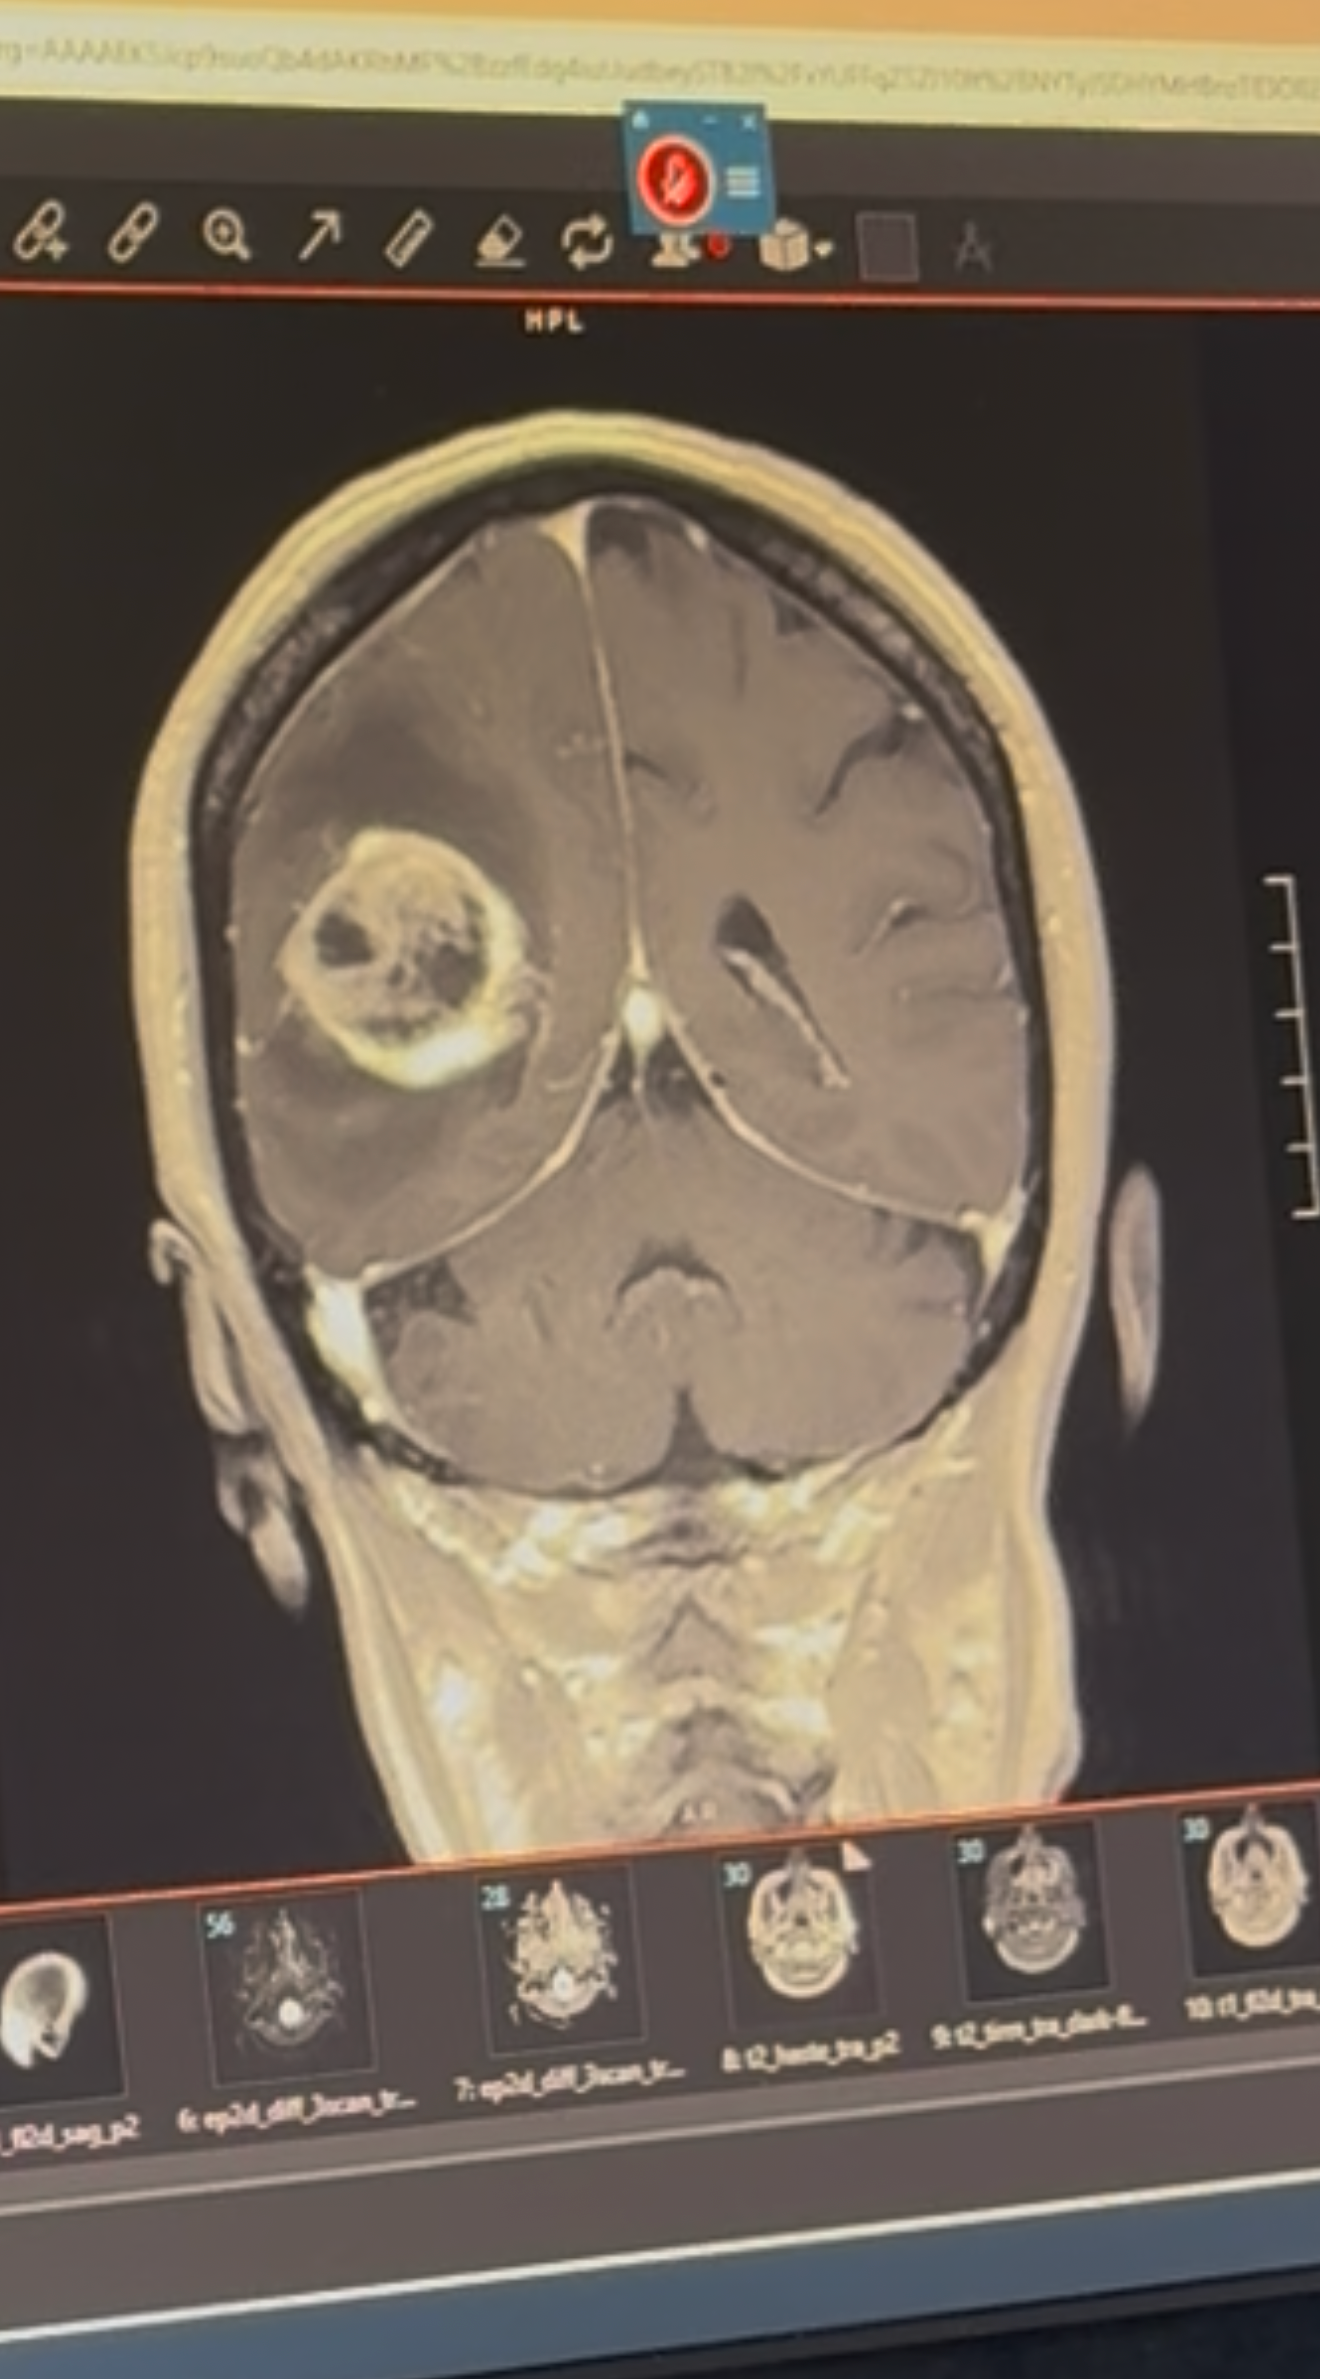

HELP ELENA FIGHT THE BATTLE AGAINST BRAIN CANCER (GLIOBLASTOMA GRADE 4)

In July 2025, I got the terrifying news that my mom, Elena, was in the hospital and had an unexpected and life-altering brain tumor. After a whirlwind of events, she underwent surgery and the results of the tumor biopsy returned as something we were hoping not to hear... Grade 4 Glioblastoma. One of the most rare and aggressive types of brain cancer.